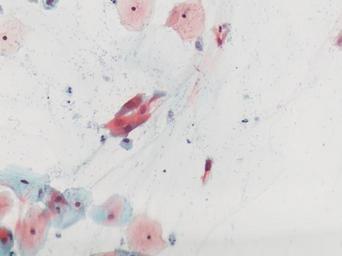

Keywords: lesión intraepitelial escamosa de bajo grado lesiónintraepitelialescamosadebajogrado citología de cuello uterino citologíadecuellouterino citología exfoliativa ginecológica citologíaexfoliativaginecológica citología de cribado citologíadecribado citología anatomía patológica anatomíapatológica bethesda 2001 bethesda2001 osuna cérvix uterino cérvixuterino hpv españa screening lsil enfermedades de transmisión sexual enfermedadesdetransmisiónsexual imágenes de citología ginecológica imágenesdecitologíaginecológica papanicolaou test de papanicolaou testdepapanicolaou tinción de papanicolaou tincióndepapanicolaou pastel Células con núcleo y citoplasma aumentado de tamaño, núcleos irregulares, como plumosos, tendencia al color naranja de muchas células, halos en algunos casos, núcleos dobles en otros, algunos núcleos hipercromáticos. Células con núcleo y citoplasma aumentado de tamaño, núcleos irregulares, como plumosos, tendencia al color naranja de muchas células, halos en algunos casos, núcleos dobles en otros, algunos núcleos hipercromáticos.